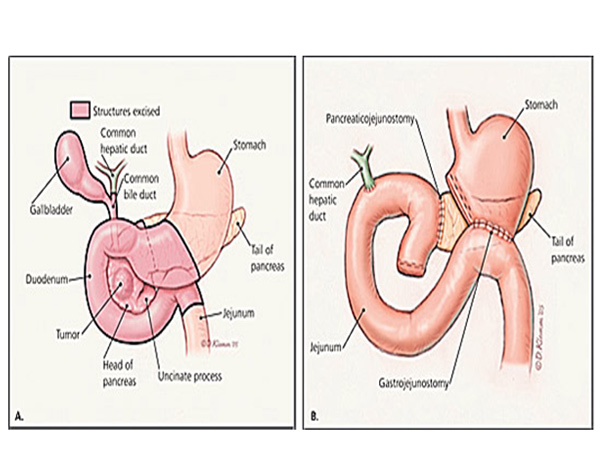

ancreas is an organ situated in the upper part of the abdomen behind the stomach. It produces digestive enzymes to help in digestion of food products and also produces insulin which is essential for sugar control. Pancreatic juices are secreted in the intestines through the main pancreatic duct. The main pancreatic duct joins the common bile duct to open into the duodenum.